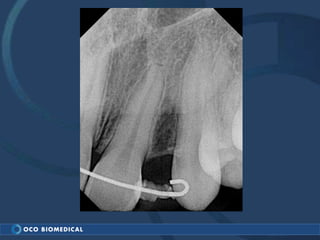

A 3.0mm dental implant was placed to replace congenitally missing maxillary lateral incisors. Dr. Tim Kosinski used a 1.8mm pilot bur and tissue punch to prepare the osteotomy site, then placed the implant by hand and seated it with a torque wrench. After ensuring the implant trajectory was within the restorative envelope, an acrylic coping was placed for temporary fabrication. At the 1 week post-op appointment, excellent soft tissue response and papilla formation were observed, and a final impression was taken to send to the lab for crown fabrication.